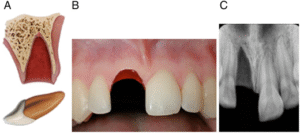

3) Pulpanın Açığa Çıktığı Kırıklar (Komplikasyonlu Kırık)

Pulpanın canlılığını korumak ve olası enfeksiyon risklerini önlemek için hızlıca tedavi edilmelidir. Diş, lokal anestezik altında pulpatomi işlemi için hazırlanılır ve MTA, CaOH gibi toksisitesi az olan olan materyallerle kapatılır ve dolgu materyalinin konulmasıyla işlem bitirilir. Dişin durumu 1 hafta sonra yeniden kontrol edilmeli, vitalitesi incelenmelidir. Daha sonrasında 6-8 haftalık periyotlarla takip sürdürülmelidir.